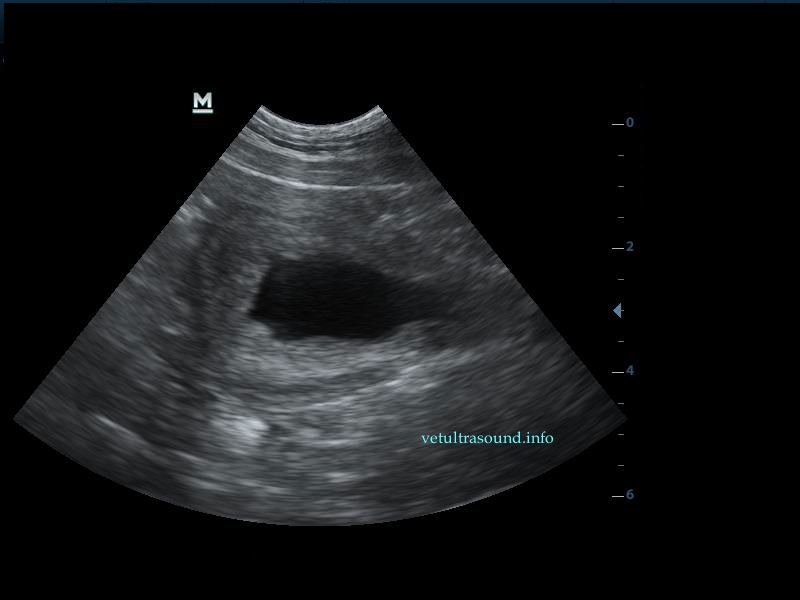

Η πάχυνση του τοιχώματος και η δοκίδωση του βλεννογόνου είναι εμφανής σε όλες τις εικόνες. Πολλές φορές οι λαγόνιοι λεμφαδένες μπορεί να είναι ήπια διογκωμένοι και να έχουν αντιδραστική ηχομορφολογία. Ο έλεγχος με έγχρωμο Doppler του τοιχώματος της άδειας κύστης μπορεί να μας δείξει ροή αίματος στα αγγεία της κύστης. Αντίθετα, είναι πιθανό, όσο η κύστη γεμίζει με ούρο η ροή αίματος να μην είναι ορατή με το Doppler. Αυτό συμβαίνει συχνά στη χρόνια βακτηριακή κυστίτιδα λόγω της ίνωσης του τοιχώματος της ουροδόχου και αυτή είναι μία από τις αιτίες της μη ανταπόκρισης στη θεραπεία. Η συγκεκριμένη παθοφυσιολογία έχει μελετηθεί στον άνθρωπο με την βοήθεια ενδοσκοπικού υπερήχου.

The increase of thickness of the urinary bladder wall and the striation of the mucosa is evident. Inguinal lymphnodes are usually prominent and mildly enlarged. Colour Doppler may reveal the blood flow of the mucosa of the empty urinary bladder, whereas the blood flow in a full bladder appears decreased. This could be because of the fibrosis of the urinary bladder wall and could explain why sometimes chronic conditions like these do not respond well to antibiotics. This pathophysiology has been studied in humans with the use of endoscopic ultrasound.